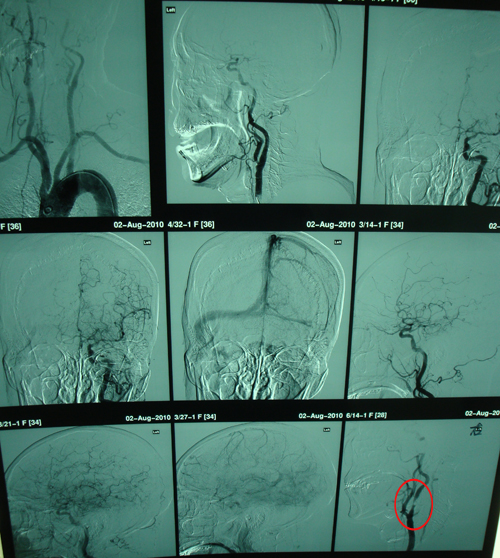

颈动脉彩超(2010-07-20北京中关村医院):双侧颈动脉内中膜增厚伴多发斑块;右颈内动脉起始段狭窄(狭窄率>90%);左侧椎动脉椎间段走行迂曲,双侧椎动脉阻力指数增高。

该患者老年男性,急性起病。有高血压病史,无明显诱因反复出现发作性言语不利,表现为吐字不清、含混,症状持续约10-20分钟,可自行缓解,查体未见明显定位体征,考虑为短暂性脑缺血发作(TIA)。查体未见明显阳性体征。颈动脉彩超发现患者右侧颈内动脉起始段狭窄>90%。无其它手术禁忌症,故行手术治疗。

2010年8月11日,由协作组张勤奕教授为其成功实施了右侧颈内动脉CEA。术后患者症状明显改善。